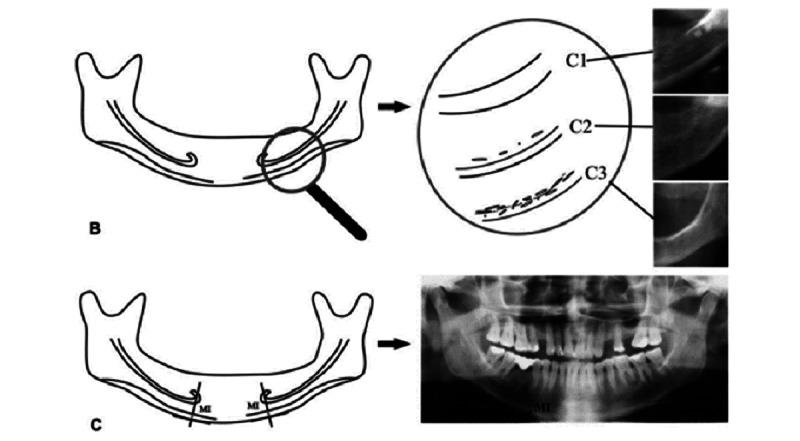

Patients aged 20 years to 40 years reporting to the Department of Oral Medicine and Radiology with and without a history of chronic areca nut chewing will be recruited. OPG will be collected for all recruited patients. The mandibular cortical index, panoramic mandibular index, gonial index, antegonial index, antegoinal notch depth, and mental index will be calculated.

招募年龄在20岁至40岁之间、有或无长期嚼槟榔史且到口腔医学与放射科就诊的患者。为所有招募的患者采集OPG。计算下颌骨皮质指数、全景下颌指数、角指数、角前切迹指数、角前切迹深度和颏孔指数。